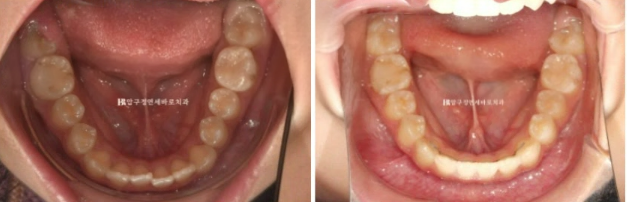

2022.12

6개월 후 정기체크를 했고 남아있던 유치가 빠지고 영구치가 올라오는 중입니다.

영구치가 완전히 올라올때까지 몇 개월 더 기다리기로 했습니다.

이후 7개월이 지났고 23년 8월에 드디어 인비절라인 교정치료 들어간 사진입니다.

23.08

장치 제작에 들어갔고 23년 9월부터 드디어 첫 세트의 1단계 장치를 끼기 시작했습니다.

약 7개월에 걸쳐 첫번째 세트를 모두 낀 후의 모습입니다.

24.03

이미 한쪽으로 쏠려버린 중심선을 얼굴 및 인중과 맞추는 교정은 간단해 보이지만 간단하지 않습니다.

어금니의 문제가 앞니까지 이어온 것이므로 한쪽 어금니 전체의 이동이 수반이 되어야 합니다.

왼쪽 위 어금니를 앞으로 끌어오기 위해서 잇몸에 교정용 미니스크류도 심고 뺏다꼈다 하는 고무줄도 쓰면서 진행했습니다.

재제작 후 추가장치에서는 작은어금니를 뿌리까지 평행하게 땡겨오기 위한 장치가 추가되었습니다.